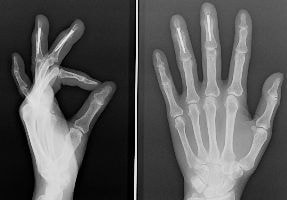

手根管症候群による母指球筋の萎縮

肘部管症候群による鷲手変形

手がしびれると、多くの方は頭や首からの症状では?と心配されるかも知れませんが、実は腕の中での神経の圧迫によるものが多いのです。これは絞扼性神経障害(こうやくせいしんけいしょうがい)と呼ばれます。

代表的なものに、更年期や出産後の女性に多い『手根管症候群』、手をよく使う男性に多い『肘部管症候群』があります。前者では手首で正中神経が圧迫され、母指・示指・中指・環指がしびれます。 症状は手指がむくむ明け方に増悪し、腱鞘炎を合併することも多いのが特徴です。後者では肘の内側で尺骨神経が圧迫され、環指・小指がしびれます。肘を曲げていると症状が増悪するのが特徴です。どちらも、神経の炎症による疼痛、感覚神経の麻痺症状であるしびれや知覚の障害、筋肉の麻痺による手指の運動障害・筋肉の萎縮を生じます。

治療は、初期には関節を動かさないよう安静を保つだけでも症状が改善することがあります。炎症による疼痛には、ステロイドの注入がよく効きます。しかしながら、麻痺症状が進行すると、これを改善させるために手術が必要になることがあります。初期の痛みが落ち着くと症状はゆっくりと進行するため、重症化してから病院を受診される方も多く、この場合には手術をしても手遅れになることがあります。

『物をよく落とす』、『箸が使いづらい』、『小さな物を摘みにくい』、などの症状が出始めたら、麻痺を残さないために早期に適切な治療を行うことが重要です。